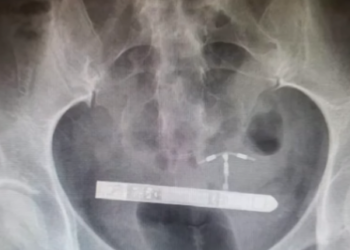

EUA - | Uma norte-americana precisou ser submetida a uma cirurgia de emergência, depois que um vibrador ficou emperrado em ...